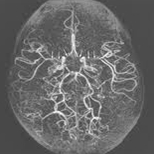

③ 뇌혈관 조영술

뇌 동정맥 기형을 확진을 할 수 있는 검사입니다. 유입 동맥, 기형의 핵, 유출 정맥을 확인할 수 있어 치료 방침을 정하는 데 많은 도움을 줍니다.